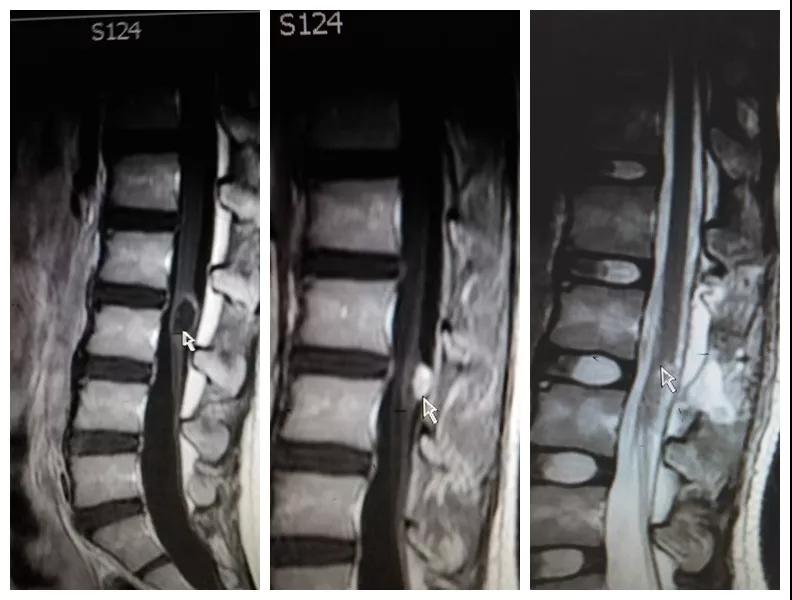

2018年8月,孩子母亲带着一线希望慕名找到六合彩生肖 神经外科王占尧主任医师。王医生通过详细询问病史、查体、完善相关检查后,明确诊断患者为腰3椎管脊髓内畸胎瘤、硬脊膜外脂肪瘤、脊髓栓系综合症、骶尾部皮毛窦。王占尧耐心与家属沟通病情及手术方式,因手术难度大费用较高患者家属有些犹豫,随后又到西安多家医院咨询,最终选择在中心医院神经外科手术。因患者椎管处有不同部位的四个病变,还伴脊髓内畸胎瘤,分几次手术安全性高但是存在再手术医疗费用高、住院时间长耽误孩子上学等问题,如果选择一次手术切除则存在手术时间长、肿瘤是否能最大限度的全切、污染手术与清洁手术同时进行等系列问题。王占尧主任医师组织医疗团队反复讨论患者病情、斟酌手术方式、评估手术风险、制定详细的手术方案,最终决定在全麻下一次手术为患者同时切除四个病变部位。孩子的父母是一辈子面朝黄土背朝天的农民,面对术前谈话时主管医生提到的种种风险,他们不能完全理解,只是落泪重复:“孩子是我两的希望,我们就把孩子交给你了王大夫!”王占尧正是承受着一旦手术失败,孩子可能原有症状加重、甚至终身大小便失禁、双下肢瘫痪的压力,带着孩子父母沉甸甸的希望走进手术室。

手术很成功。术后孩子恢复非常好,未出现并发症,复查磁共振肿瘤切除干净,大小便失禁症状较术前明显好转,腰部疼痛也得到了缓解,目前已痊愈出院。